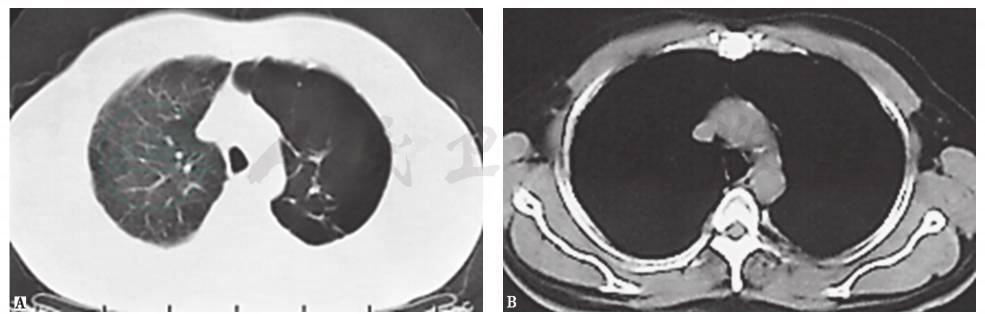

入院1个月前,胸部CT见左侧多发肺大疱,左下肺脓肿,其内见液平,左主支气管腔内高密度影,左侧少量胸腔积液(图1),抗感染治疗后未见好转(图2)。

图1 1个月前胸部CT表现

4.影像学检查显示左肺过度充气,多发肺大疱,其内可见气液平,左主支气管腔内可见钙质密度占位影。